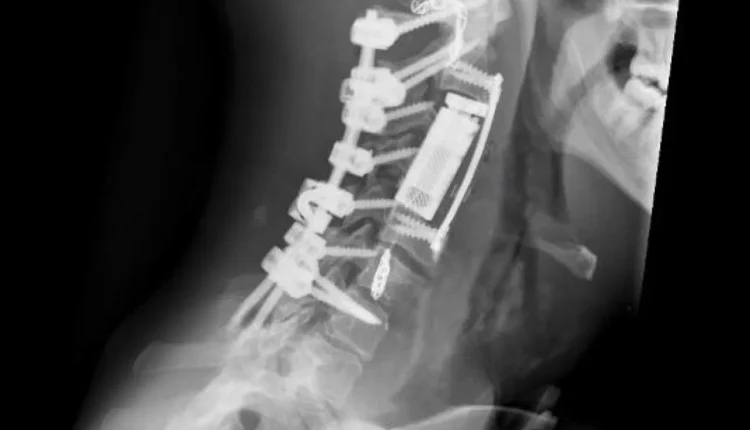

وفي المرحلة الجراحية، تم إجراء تثبيت خلفي للعمود الفقري من الفقرة العنقية الأولى وحتى السابعة، مع تحرير النخاع الشوكي وتأمين استقرار الفقرات، وبعد ذلك، أُجري استئصال كامل للورم والفقرات المصابة بطريقة “الاستئصال الكامل في كتلة واحدة” عبر المدخل الأمامي للعنق، تلاه تعويض الفقرات باستخدام قفص فقري تمددي، مع تثبيت أمامي لضمان الثبات الكامل للعمود الفقري.

وأكد البربراوي أن هذه العملية تُعد الأولى من نوعها في الأردن والمنطقة، ولا تُجرى إلا في المراكز المتقدمة على مستوى العالم، نظرًا لتشريح الورم المعقد، إذ شملت استئصال أكثر من فقرة عنقية إضافة إلى الشريان الفقري المصاب المجاور للورم.